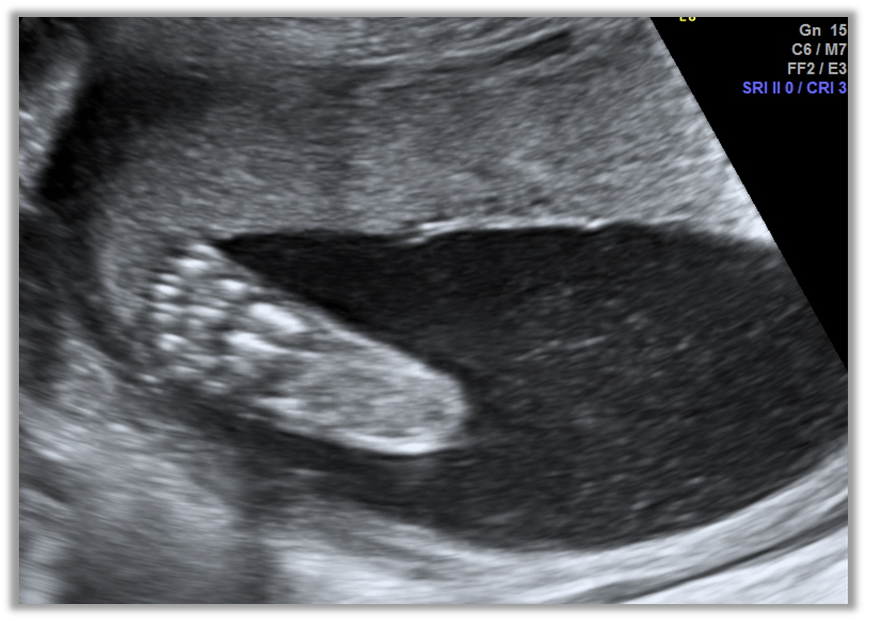

Достоверной оценкой, позволяющей быстро, точно, неинвазивно и в режиме реального времени измерить объем АЖ является ультразвуковое исследование (УЗИ (3)

Рекомендована оценка АЖ как неотъемлемая часть рутинного анатомического исследования парафетальных структур, которая должна проводиться при всех ультразвуковых исследованиях плода (1,8,43).

Рекомендовано до 18 недель беременности оценивать объем АЖ субъективно или с помощью определения МВК. После 18 недель также может рассчитываться ИАЖ (при многоплодии используется только МВК![1]). Полуколичественная оценка предпочтительнее субъективной из-за воспроизводимости, а также возможности оценивать изменения в процессе динамического наблюдения (8).

Методика проведения полуколичественной оценки объема амниотической жидкости с определением МВК включает следующие особенности (1,8):

удержание ультразвукового датчика перпендикулярно положению матери;

определение четких границ верхнего и нижнего краев кармана жидкости;

измерение максимального свободного кармана амниотической жидкости, имеющего ширину более 1 см;

использование цветового допплеровского картирования для установления отсутствия пуповины, когда ее отсутствие вызывает сомнения.

ИАЖ рассчитывается путем суммирования величины четырех вертикальных карманов амниотической жидкости, по одному в каждом квадранте матки (8)